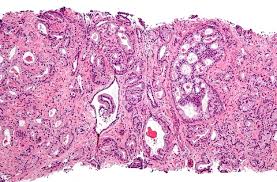

Many prostate cancers grow slowly and are confined to the prostate gland, where they may not cause serious harm. Adenocarcinomas are cancers that develop in the gland cells that line the prostate gland. It's so common that it sometimes doesn't go diagnosed until autopsies are performed, though that doesn't mean the cancer is. Therefore, the most common type of prostate cancer is an adenocarcinoma. Other risk factors include obesity, diets high in saturated fats, high testosterone levels or a family history of prostate cancer.

Prostate Cancer World Cancer Research Fund International from www.wcrf.org In theory, prostate cancer cells can spread anywhere in the body. The most common risk factor is age. Prostate cancer is one of the most frequently diagnosed cancers in the world, despite it only being diagnosed in males (females do not have prostate glands).in fact, more than 70 percent of men over the age of 80 have some quantity of cancer cells in their prostate. 3 these may be signs your cancer has spread to your spine or your liver, respectively. The information below will give you more insight into prostate cancer symptoms in men. So it's helpful to know the most common types of cancer and their warning signs. Other risk factors include obesity, diets high in saturated fats, high testosterone levels or a family history of prostate cancer. Adenocarcinomas are cancers that develop in the gland cells that line the prostate gland.